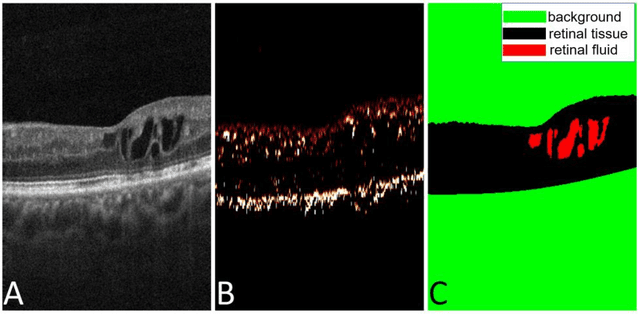

Abstract:Purpose: We proposed a deep convolutional neural network (CNN), named Retinal Fluid Segmentation Network (ReF-Net) to segment volumetric retinal fluid on optical coherence tomography (OCT) volume. Methods: 3 x 3-mm OCT scans were acquired on one eye by a 70-kHz OCT commercial AngioVue system (RTVue-XR; Optovue, Inc.) from 51 participants in a clinical diabetic retinopathy (DR) study (45 with retinal edema and 6 healthy controls). A CNN with U-Net-like architecture was constructed to detect and segment the retinal fluid. Cross-sectional OCT and angiography (OCTA) scans were used for training and testing ReF-Net. The effect of including OCTA data for retinal fluid segmentation was investigated in this study. Volumetric retinal fluid can be constructed using the output of ReF-Net. Area-under-Receiver-Operating-Characteristic-curve (AROC), intersection-over-union (IoU), and F1-score were calculated to evaluate the performance of ReF-Net. Results: ReF-Net shows high accuracy (F1 = 0.864 +/- 0.084) in retinal fluid segmentation. The performance can be further improved (F1 = 0.892 +/- 0.038) by including information from both OCTA and structural OCT. ReF-Net also shows strong robustness to shadow artifacts. Volumetric retinal fluid can provide more comprehensive information than the 2D area, whether cross-sectional or en face projections. Conclusions: A deep-learning-based method can accurately segment retinal fluid volumetrically on OCT/OCTA scans with strong robustness to shadow artifacts. OCTA data can improve retinal fluid segmentation. Volumetric representations of retinal fluid are superior to 2D projections. Translational Relevance: Using a deep learning method to segment retinal fluid volumetrically has the potential to improve the diagnostic accuracy of diabetic macular edema by OCT systems.